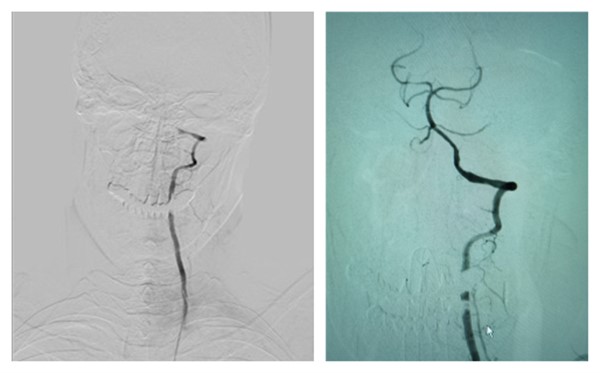

神经内科介入技术再上新台阶——完成一例超长节段非急性期椎基底动脉闭塞再通治疗

脑卒中已逐步成为我国第一致死原因;其中缺血性卒中占80%左右,20%由椎-基底动脉病变引起。强化药物治疗非急性椎-基底动脉闭塞,大约80%的病人会有不良预后,病死率可达40%,而约65%的幸存病人会遗留不同程度的残疾。...